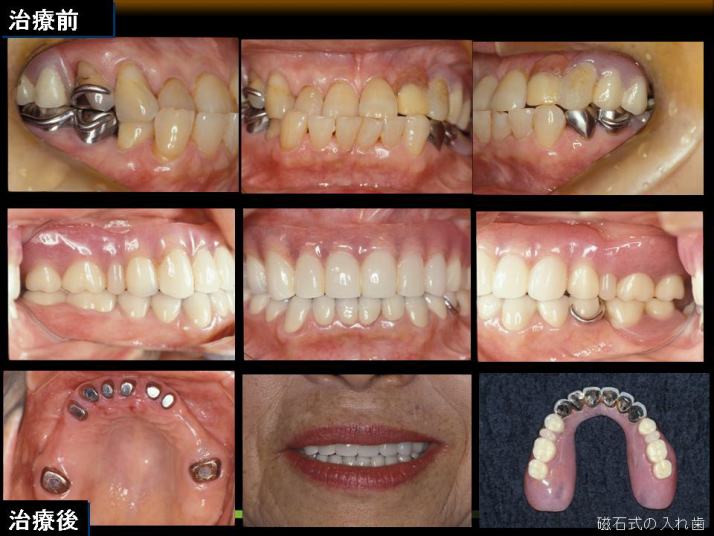

磁石式入れ歯

オーダーメイドの義歯の一例として磁石義歯(磁性アタッチメント義歯)が挙げられます。

残っている自分の歯やインプラントに磁石と相性のいい金属を、入れ歯のほうに超小型磁石を取り付けることで、 磁力によりガタつきのないぴったりとフィットする入れ歯です。 (残念ながら保険適応外です)

磁石義歯 噛み合わせの問題で入れ歯がありましたが、磁石の入れ歯で改善しました

磁石義歯

当院での治療例(クリックで拡大)

御自分の歯とインプラントに磁性アタッチメントを応用した症例